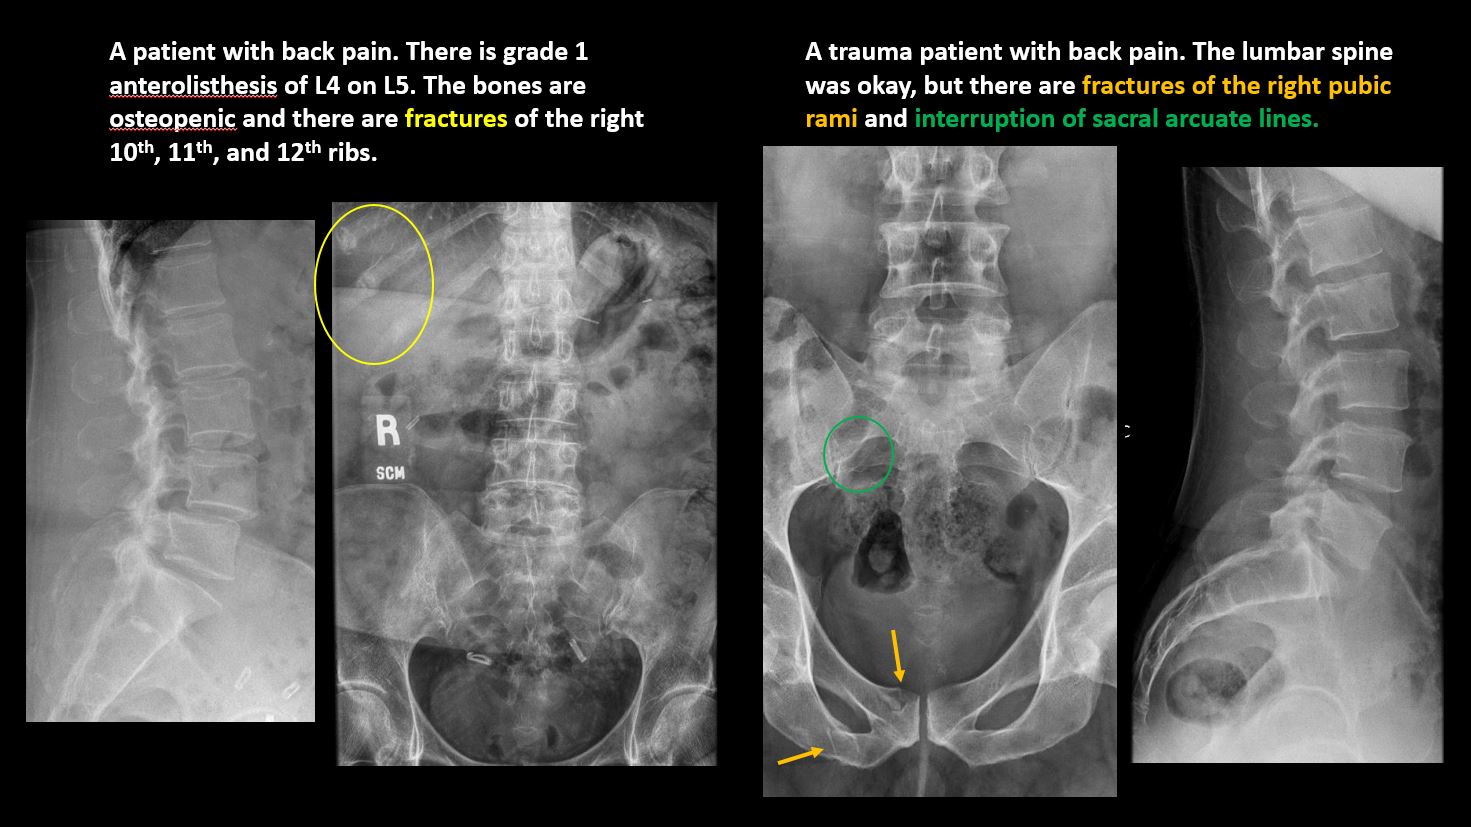

There is a fracture or interruption of the arcuate lines of the sacrum. [Yes/No]

There is focal or diffuse abnormal mineralization of the lumbosacral spine. [Yes/No]

The included thoracic spine, ribs, and remainder of the bony pelvis are abnormal. [Yes/No]